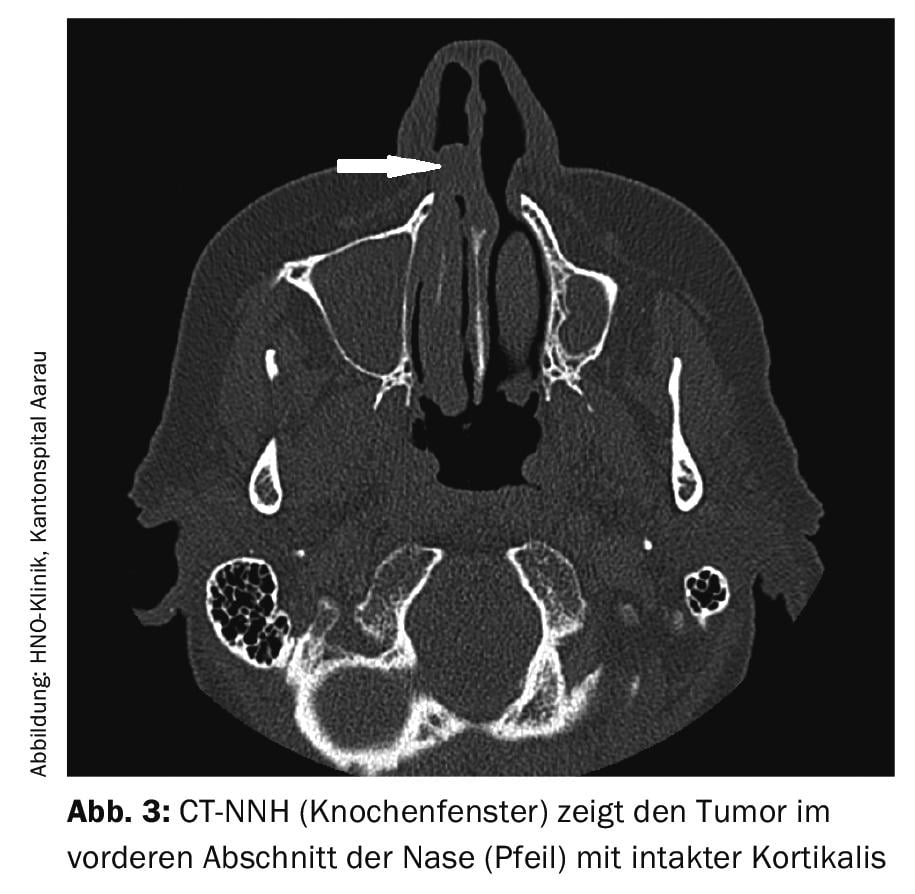

La resonancia magnética es significativamente más específica que la tomografía computerizada para el diagnóstico del melanoma maligno. Esto se debe a las propiedades paramagnéticas de la melanina. A menudo, el diagnóstico debe complementarse con una tomografía computarizada para evaluar la posible invasión de estructuras óseas (Fig. 3).